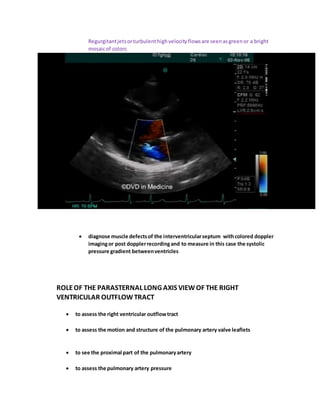

Regurgitantjetsorturbulenthighvelocityflowsare seenasgreenor a bright

mosaicof colors

 diagnose muscle defectsof the interventricularseptum withcolored doppler

imagingor post dopplerrecordingand to measure in this case the systolic

pressure gradient betweenventricles

ROLEOF THE PARASTERNAL LONG AXIS VIEWOF THE RIGHT

VENTRICULAR OUTFLOWTRACT

 to assess the right ventricular outflowtract

 to assess the motion and structure of the pulmonary artery valve leaflets

 to see the proximal part of the pulmonaryartery

 to assess the pulmonary artery pressure